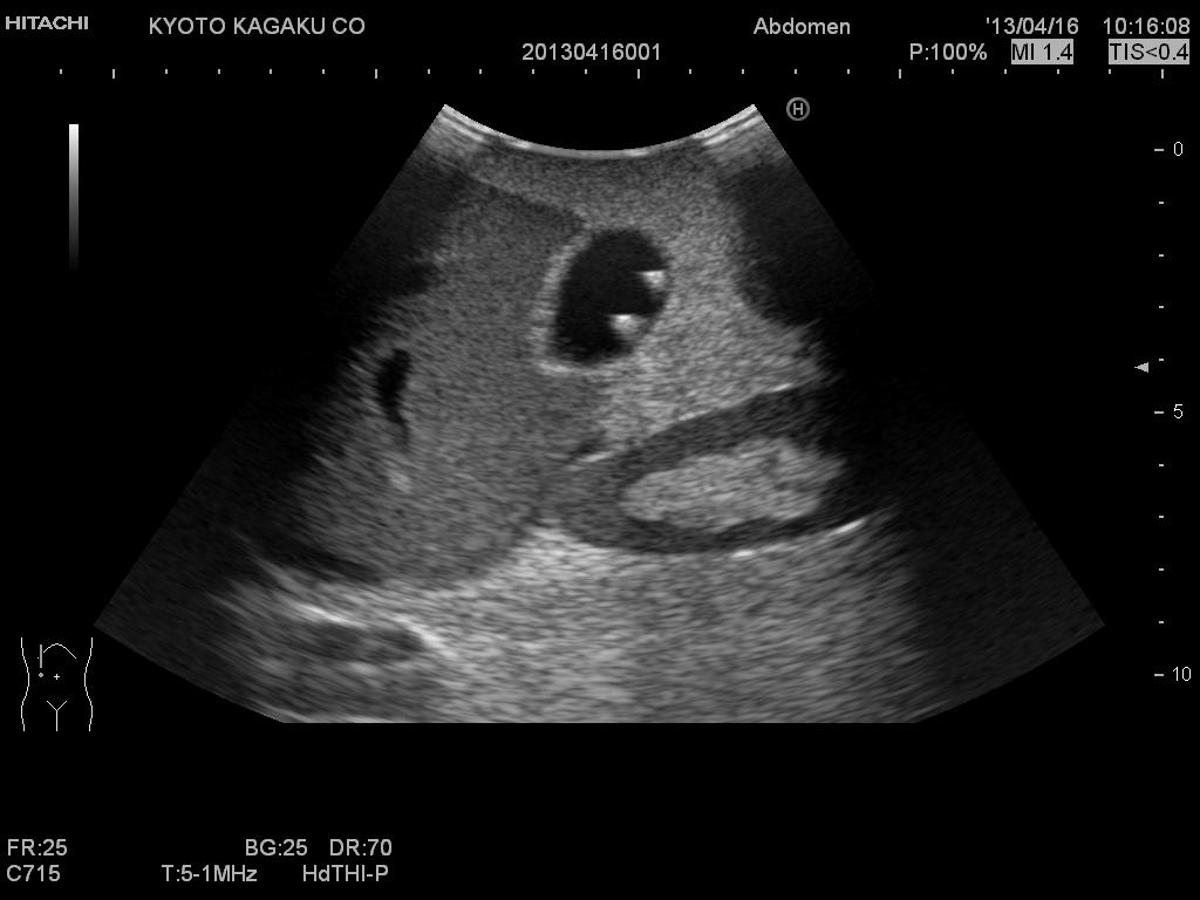

The Paediatric FAST/Acute Abdomen Phantom facilitates the practice of hands-on training using ultrasound to examine young patients. Using FAST procedures, trainees are able to identify internal haemorrhage at the perihepatic, perisplenic, pelvis, and pericardium area, whilst the ultrasound capabilities of the module allow for bowel intussusception, appendicitis and biliary dilatation recognition.

Using FAST procedures to identify Internal hemorrhage at the perihepatic, perisplenic, pelvis, and pericardium area

Sonography for acute paediatric patient, helping to identify bowel intussusception, appendicitis and biliary dilatation